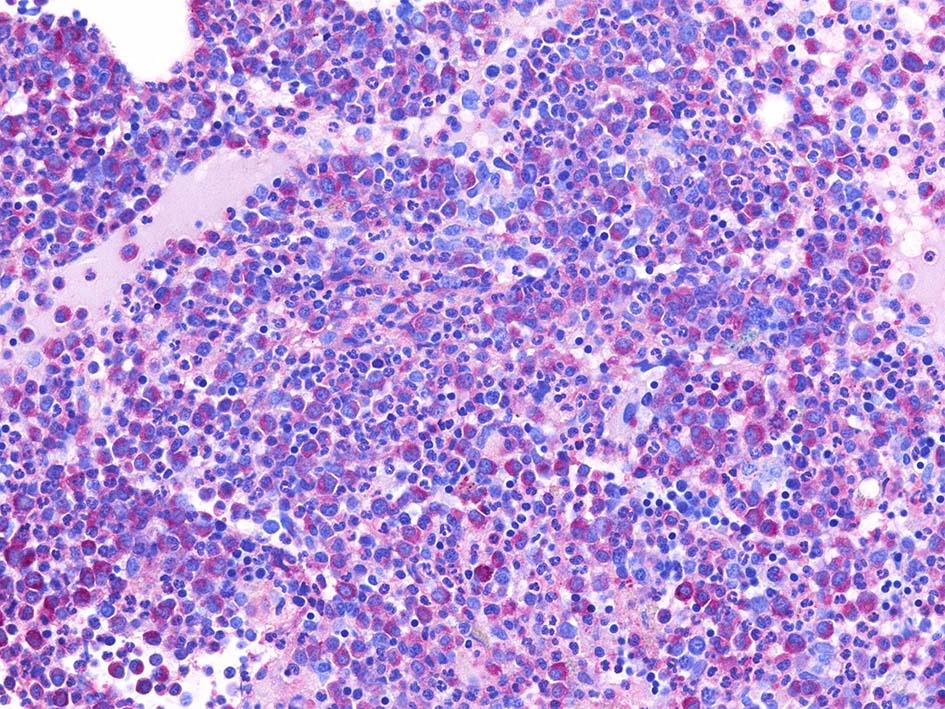

Fig.03: granulopoietic hyperplasia. 成熟顆粒球の増加もある.